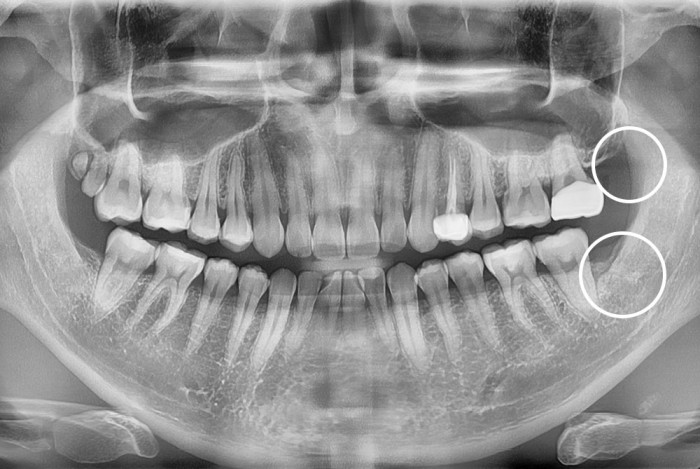

[사랑니] 매복 사랑니 발치

치료후 : 2021-08-27

세종치과는 구강악안면외과학 박사이신 원장님이 발치하는 치과입니다.